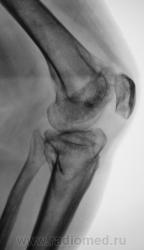

Консолидированый перелом проксимального эпифиза большеберцовой кости с повреждением наружного мениска и крестообразных связок ( вернее после их пластического восстановления ).

Александр Викторович,стояние отломков можно считать удовлетворительным?.+ вторичный ДОА+"пятнистый" остеопороз с участками остеосклероза.

стояние отломков, по истечении года, большого значения уже не имеет, главное что консолидация наступила, связочный аппарат восстановлен, в данном случаи нужно оценивать функцию, опорность, объем движений в данном суставе. Хотя внутренний мыщелок б\б кости просел прилично...